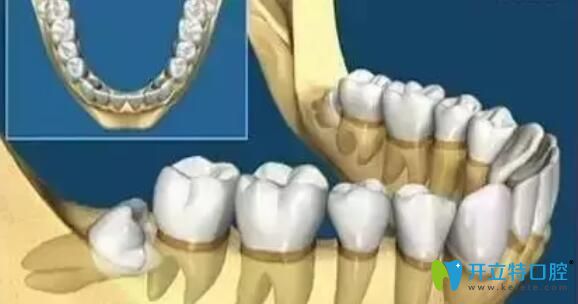

牙齒在頜骨內(nèi)由于位置不正,不能萌出到正常的咬合位置,這樣的牙齒稱為阻生牙。常見的阻生齒是下頜第三磨牙(智齒),其次是上頜第三磨牙(智齒)和上頜尖牙。所以阻生牙不一定是智齒,也可能是其它牙齒,如果智齒萌出正常,則不能稱為阻生牙。

阻生牙是因?yàn)樯L(zhǎng)的位置不當(dāng),因此往往會(huì)以很多“出人意料”的姿勢(shì)生長(zhǎng),這種使得牙齒之間很容易藏污納垢和滋生細(xì)菌,并且很容易引起口臭、齲壞等,如果是阻生智齒,宜盡早拔除,以下情況建議拔除。